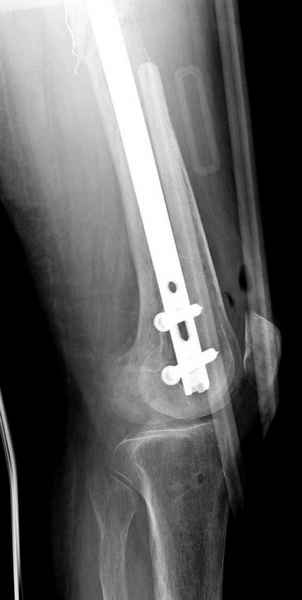

Здесь случай 66 летней пациентки со спонтанными болями в левой нижней конечности, обратилась в приемное, сделаны снимки бедра и КТ.

Патологический перелом бедра, конечность на вытяжении.

Со слов, больная ничем не болела, только последние 3 месяцев чувствовала боли в бедренной области. КТ брюшной полости подтвердил увеличенную правую почку. (5-6)

Для предупреждения кровотечения во время рассверливания, за день до операции провели эмболизацию сосудов питающий метастаз. http://radiology.rsnajnls.org/cgi/reprint/150/3/673.pdf (7-11, 12-15-16)

С минимальным рассверливанием и ретроградным методом провели остеосинтез бедра 12 мм гвоздем. (17-20)

Кровопотеря во время операции меньше 100 мл.